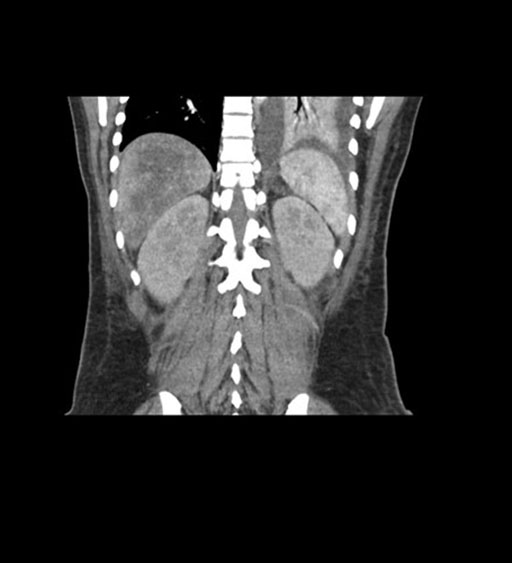

Coronal Arterial

Coronal Venous

Imaging analysis

Based on initial findings, which issue(s) would you be most concerned about?